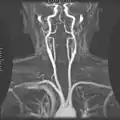

Angiograma por resonancia magnética.